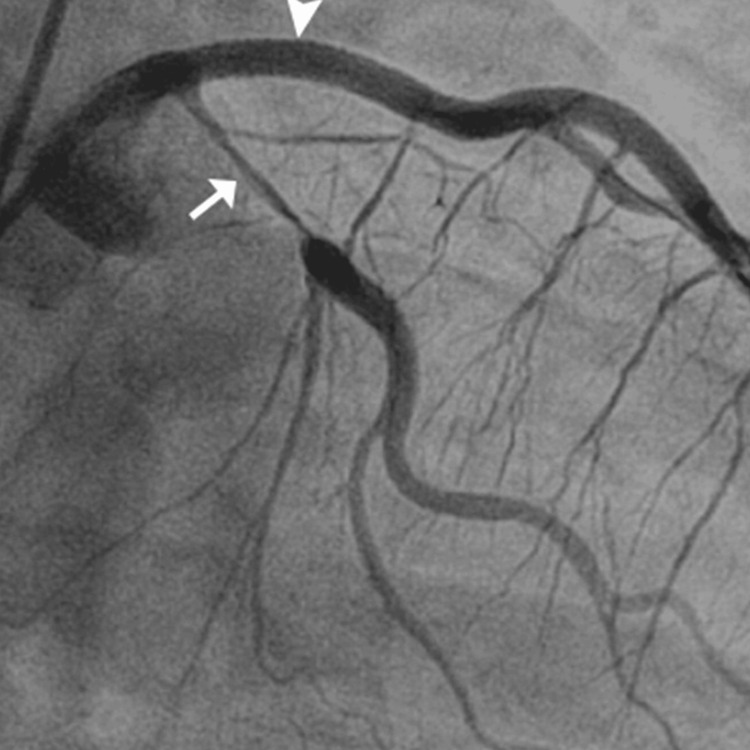

Further diagnostic investigation was pursued through cardiac catheterization, which uncovered a diffuse dissection involving the mid-distal portion of the LAD artery, the posterior descending artery (PDA), the second diagonal branch of the LAD, and the first obtuse marginal branch (OM1) of the left circumflex artery. These findings confirmed the diagnosis of SCAD. The echocardiogram supported these findings showing a left ventricular ejection fraction (LVEF) between 35% and 40% and a fixed mural thrombus on the apical wall of the left ventricle, which are indicators of significant cardiac dysfunction.

The patient’s urine toxicology screen returned positive for Δ9-THC, indicating recent marijuana use, which could have contributed to his cardiovascular event given the known hemodynamic effects of cannabinoids. The angiographic findings illustrating the progression and extent of the coronary artery dissections are sequentially shown in Figures 1–3, providing visual confirmation of the clinical and diagnostic narrative described above.